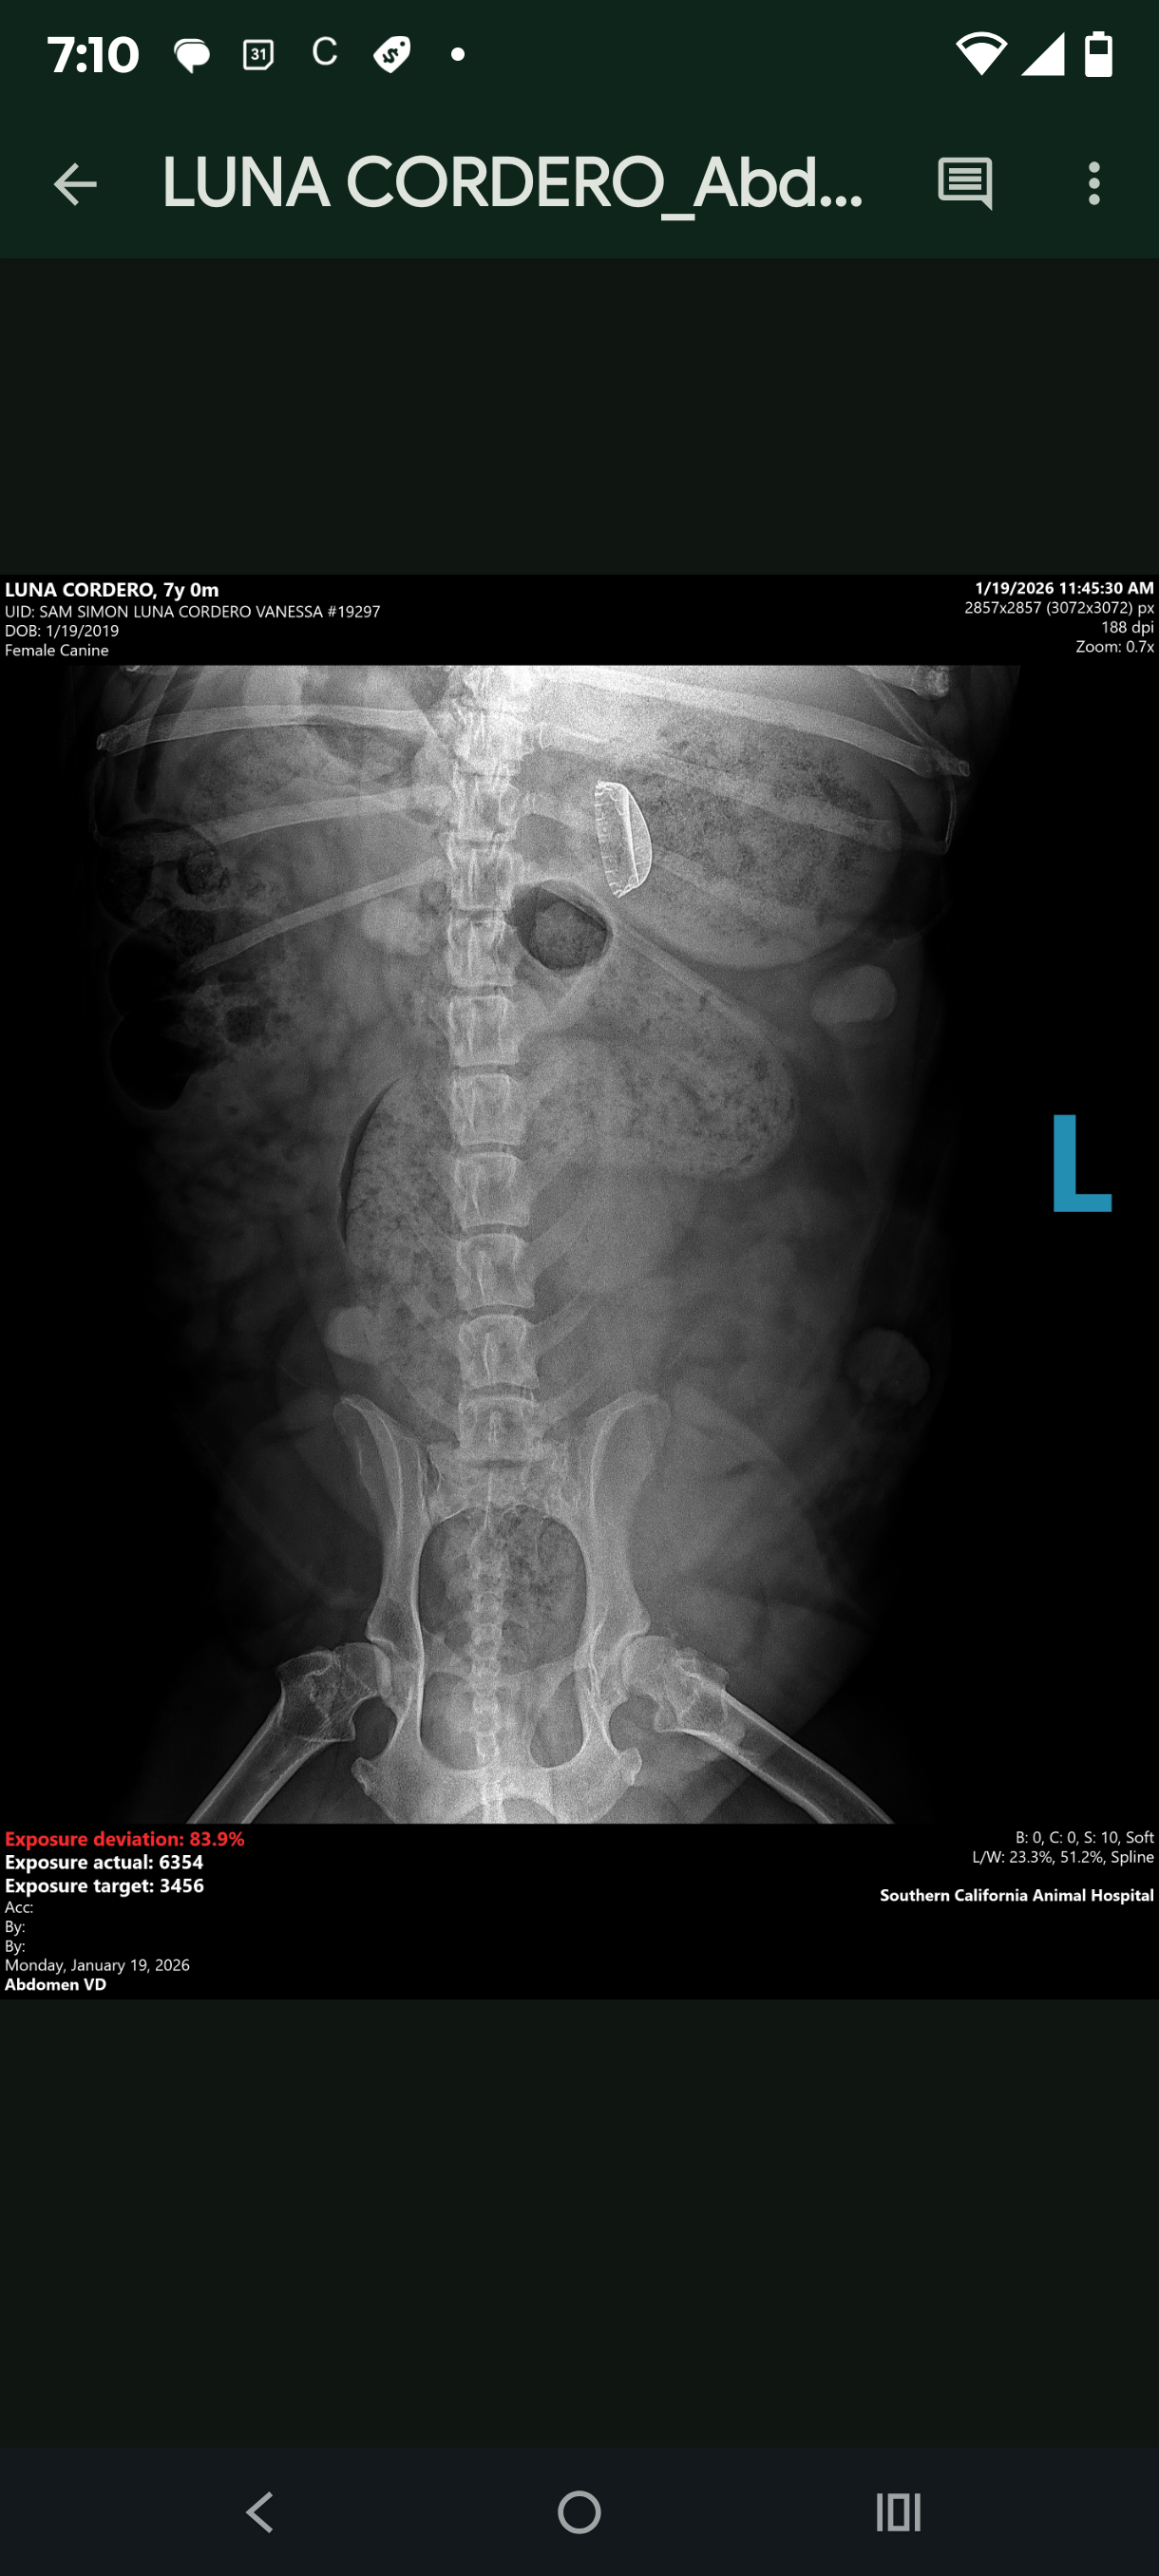

UPDATE: she has been to the vet and after the x-rays we have found a metal bottle cap in her stomach. We don't know how long it's been there. So her surgery is even extra urgent after this new information. She also has arthritis in her spine and her teeth are broken and her dew claws have been removed. This poor girl has really been abused. Please help us spread the word to get her the surgery she needs.